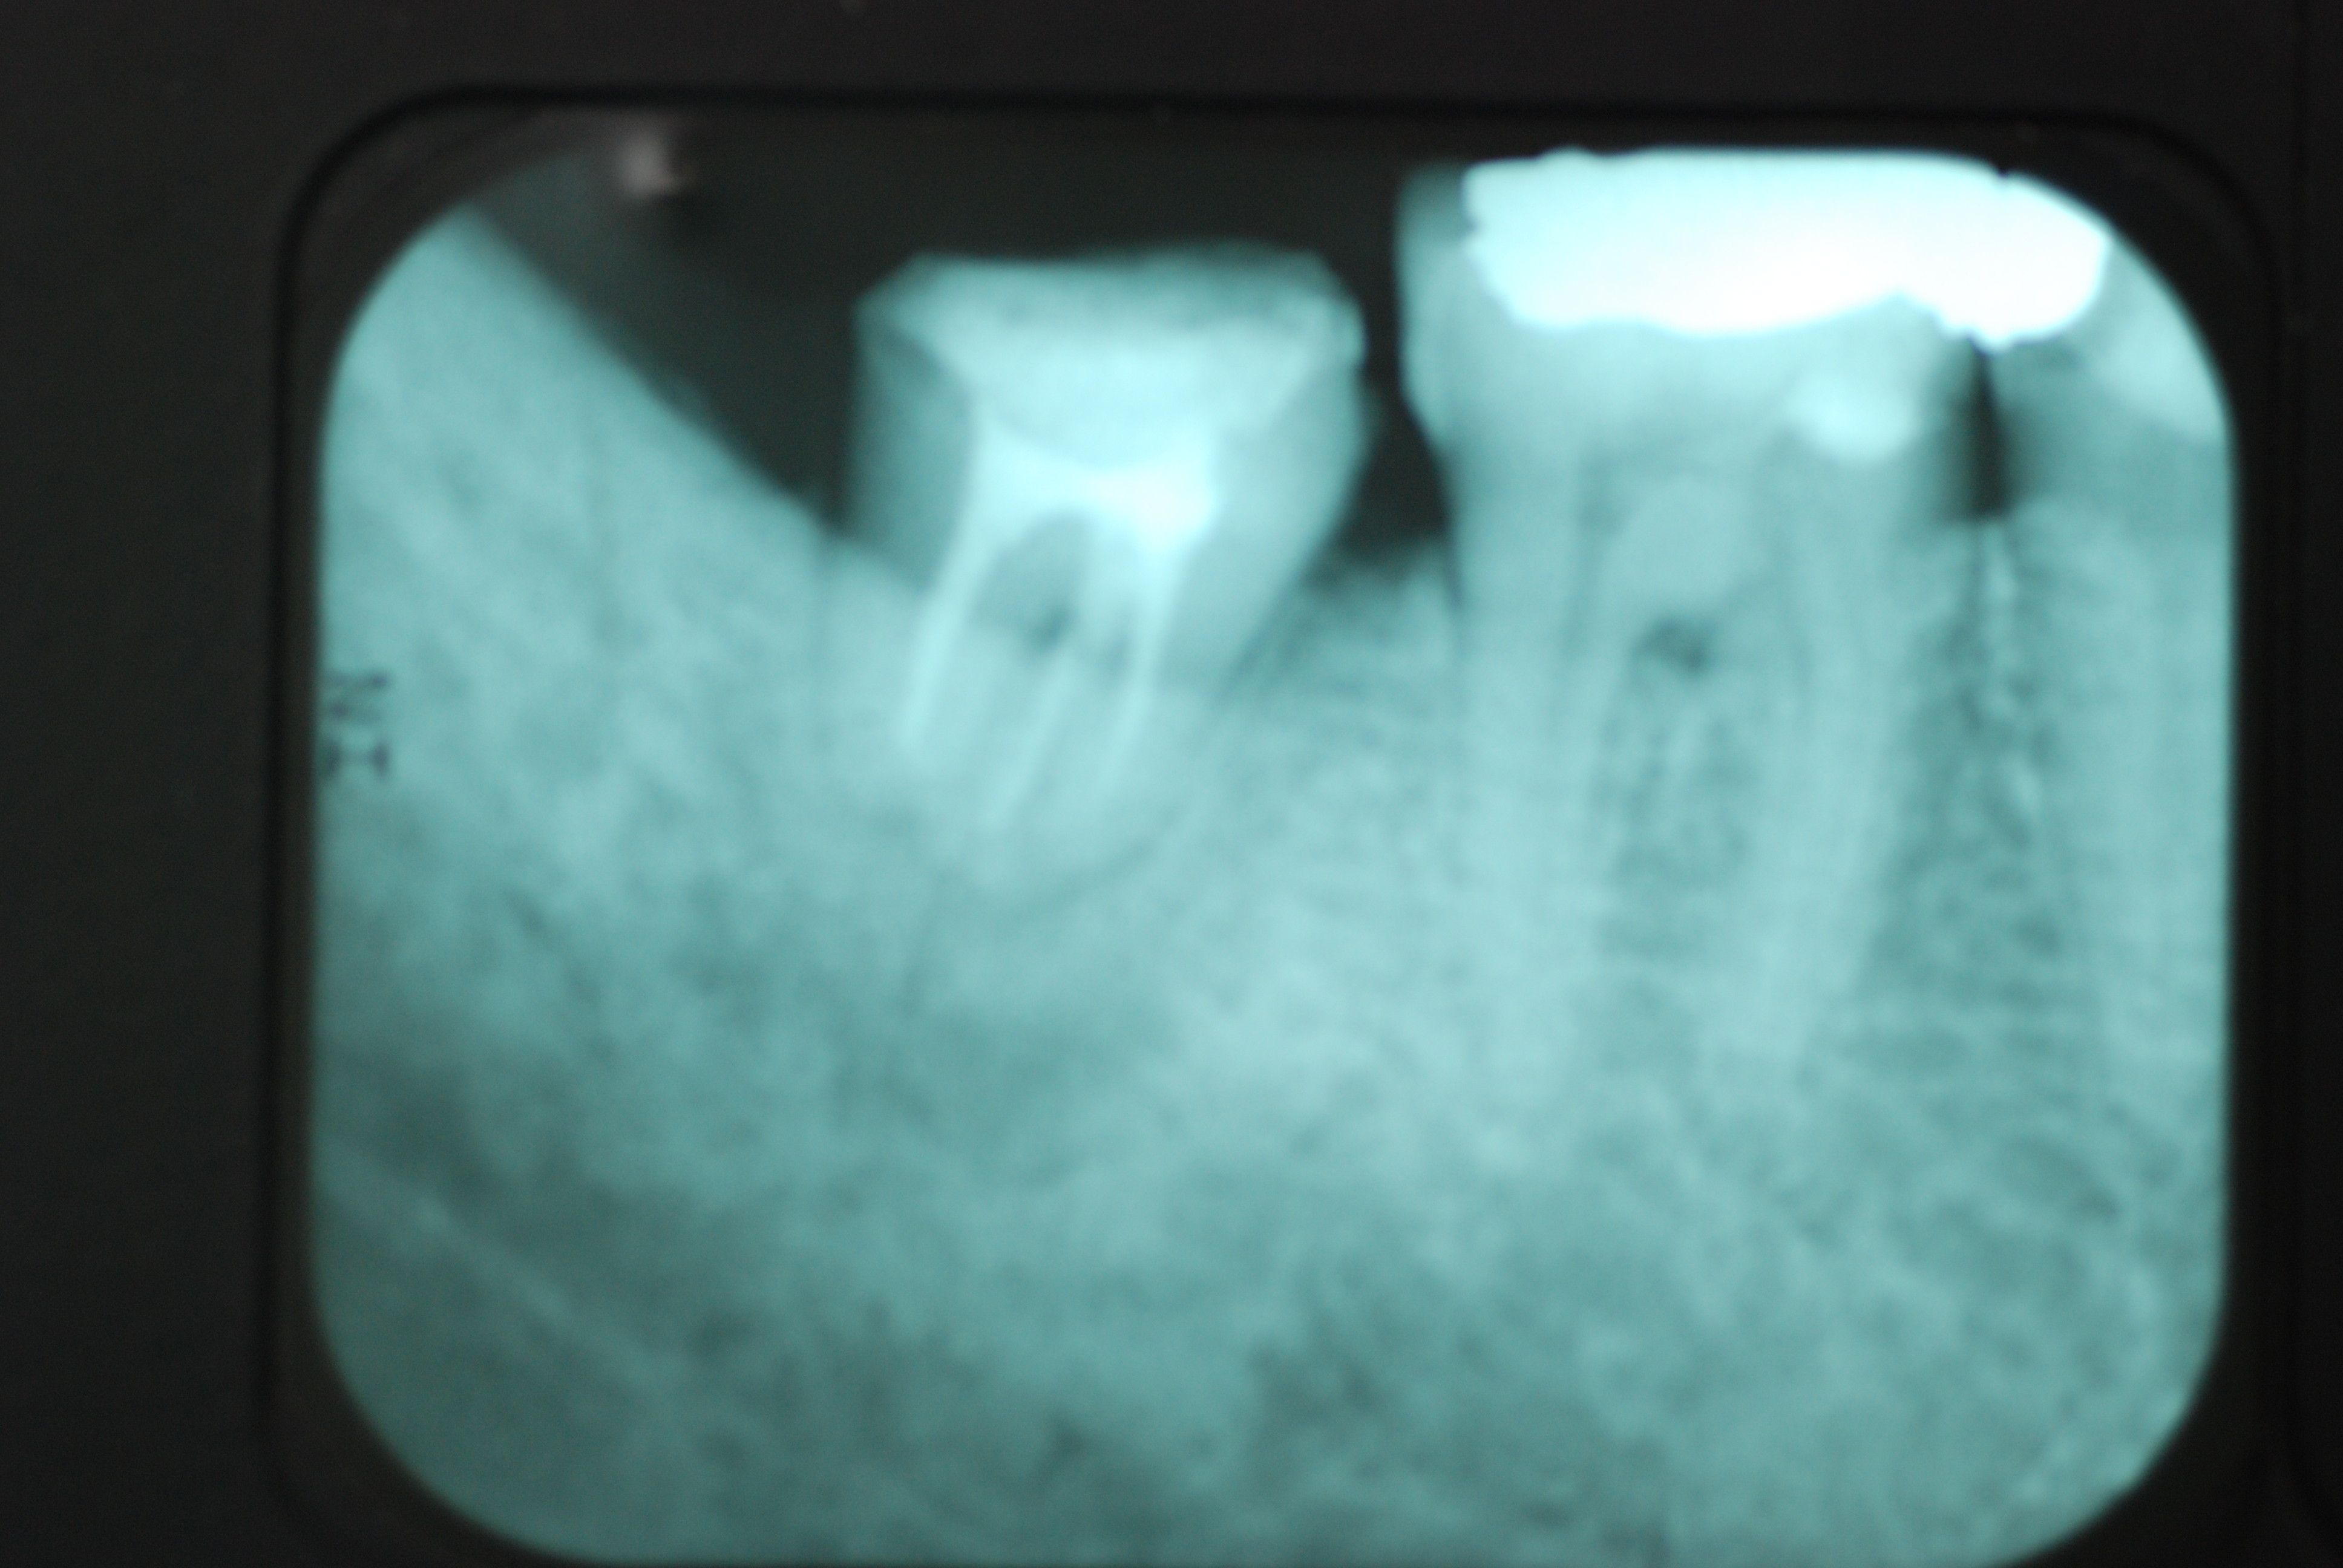

反対側の大臼歯には分岐部に深い虫歯と深い分岐部病変がありますが、虫歯の治療後は歯周病が酷いのに来られなくなりました。

上のレントゲンでも歯根の間に影があります。悪性の分岐部病変ですね。